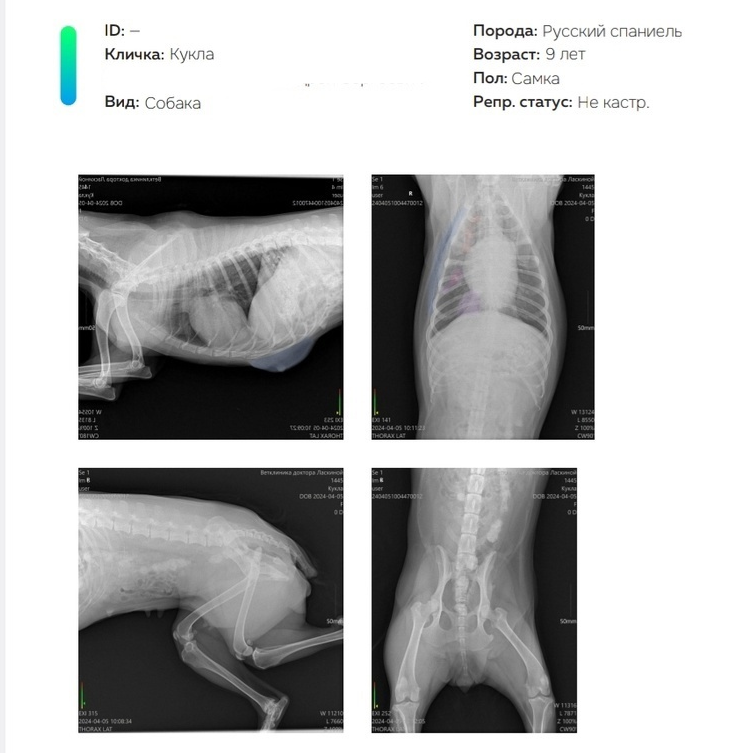

русский спаниель рентген

фото: Ветеринарная клиника Варга, г.Лысьва

После рентгена выяснилось, что у русского спаниеля по кличке Кукла ушиб грудной клетки, правого лёгкого и брюшной полости, перелом рёбер справа. «Это просто чудо, что не сломан позвоночник и нет переломов конечностей!» — написали ветврачи, добавив, что состояние животного «стабильно тяжёлое». Сейчас собака находится под присмотром волонтёров.